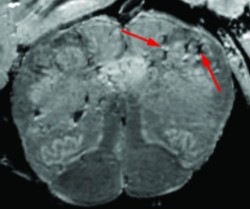

코로나19로 사망한 환자의 뇌 사진/미국 국립보건원

미국 국립보건원은 3~7월에 코로나19를 겪고 사망한 환자 19명을 대상으로 뇌 조직 샘플을 채취해 검사했다. 그 결과, 코로나19로 사망한 환자의 뇌 혈관이 얇아지고 손상됐다. 뇌 조직에서 코로나19의 병원균인 SARS-CoV-2 징후가 안 보였는데, 이는 바이러스가 뇌를 직접 공격한 것은 아니라는 의미다. 연구팀은 "코로나19에 감염되면 신체가 염증 반응을 일으키고, 이로 인해 뇌가 취약해져 혈관 손상을 입게 된다고 본다"고 말했다.